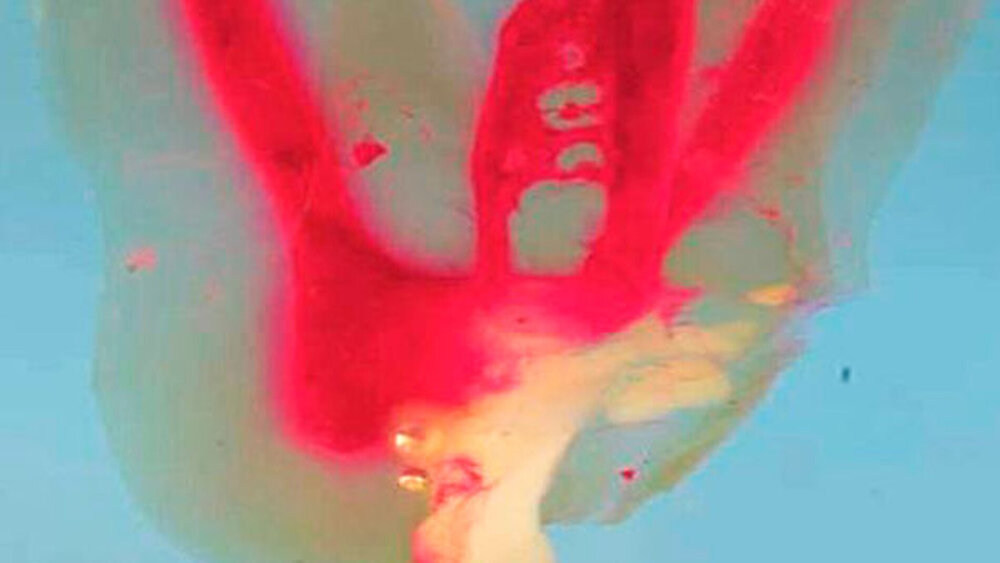

In der Vergangenheit halfen histologische Untersuchungen an Zahnhartgewebeschliffen, die Anfertigung von transparenten Zahnpräparaten mit injizierter Tusche [Vertucci, 1984; Reuver, 2018iD] und vergrößerte Rekonstruktionen aus Wachs, die Vielfalt und Variabilität des Wurzelkanalsystems darzustellen und Ursachen für Misserfolge endodontischer Therapien zu ermitteln [Carabelli, 1844; Black, 1902]. Noch heute findet die Anwendung der Transparenzmethode große Aufmerksamkeit, da sie die anatomische Variabilität von Wurzelkanalsystemen dreidimensional abbilden kann (Abbildung 1).

Danksagung: Für die Herstellung und fotografische Dokumentation der transparenten Präparate der Abbildung 1 gebührt der herzlichste Dank Dr. Holm Reuver aus Neustadt/Weinstraße.